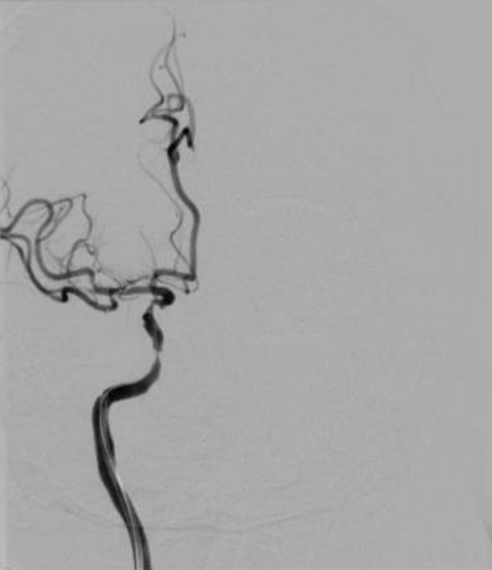

导丝怎么扩【载药时代 球扩天下】NOVA DES®颅内药物洗脱支架在颈内动脉颅内段重度狭窄中的应用体会二例!_https://www.jmylbn.com_新闻资讯_第22张

导丝怎么扩【载药时代 球扩天下】NOVA DES®颅内药物洗脱支架在颈内动脉颅内段重度狭窄中的应用体会二例!_https://www.jmylbn.com_新闻资讯_第23张

重要影像结论:右侧椎动脉V1段中度狭窄;右侧椎动脉V4段重度狭窄;左侧椎动脉V4段中度狭窄。